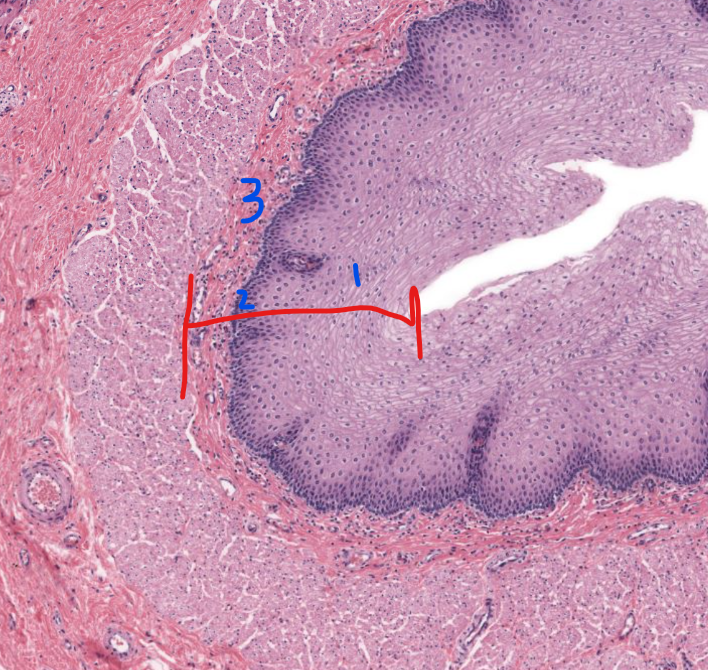

1

stratified squamous non-keratinized epithelium of esophagus

2

lamina propria of esophagus

3

muscularis mucosa of the esophagus